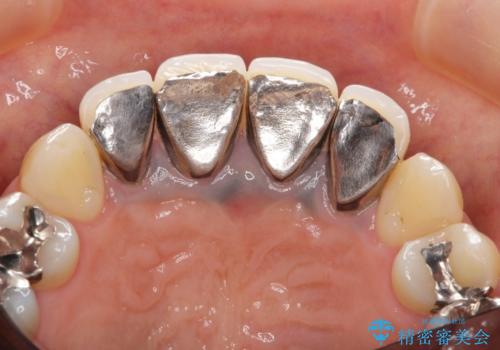

- 歯ぐきの黒っぽさ、暗い色調の前歯の改善を求めて来院されました。

金属を用いたコア・クラウンが装着されており、全ての金属を除去したのちのメタルフリー治療を計画します。